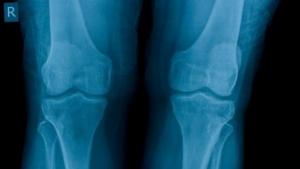

Kolagen snižuje bolesti i degeneraci kloubů

Měli jste někdy pocit, že máte "dřevěné nohy", tedy nohy ztuhlé a navíc vás každý pohyb bolel? Pokud ano, je pravděpodobné, že přicházíte o kolagen. Protože když ztrácíme kolagen, dávají se naše šlachy a vazy do pohybu těžší, což vede k ztuhlosti, otokům kloubů a dalším problémům.

Se svou gelovitou, hladkou strukturou, která pokrývá a drží naše kosti pohromadě, nám kolagen umožňuje hýbat a pohybovat se bez bolesti. Představte si užívání kolagenu jako namazání vrzajících pantů na dveřích. Pomůže vašim kloubům snadněji se pohybovat, zmírňuje bolest související se stárnutím a dokonce snižuje riziko poškození kloubů. Není pak divu, že nedávná studie zjistila, že je kolagen účinnou léčbou na ošetřování osteoartritidy a jiných bolestí a problémů kloubů.

Vědci v jedné studii zjistili, že suplementace kolagenu typu 2 pomohla pacientům trpícím na revmatoidní artritidu. Ulevilo se jim od bolesti kvůli zmírnění otoku kloubů. Další studie zjistila, že se u lidí s osteoartritidou po léčbě kolagenem 2. typu výrazně zlepšila schopnost vykonávat každodenní činnosti, jako je chůze do schodů či ze schodů, spánek a došlo k celkovému zlepšení jejich kvality života.